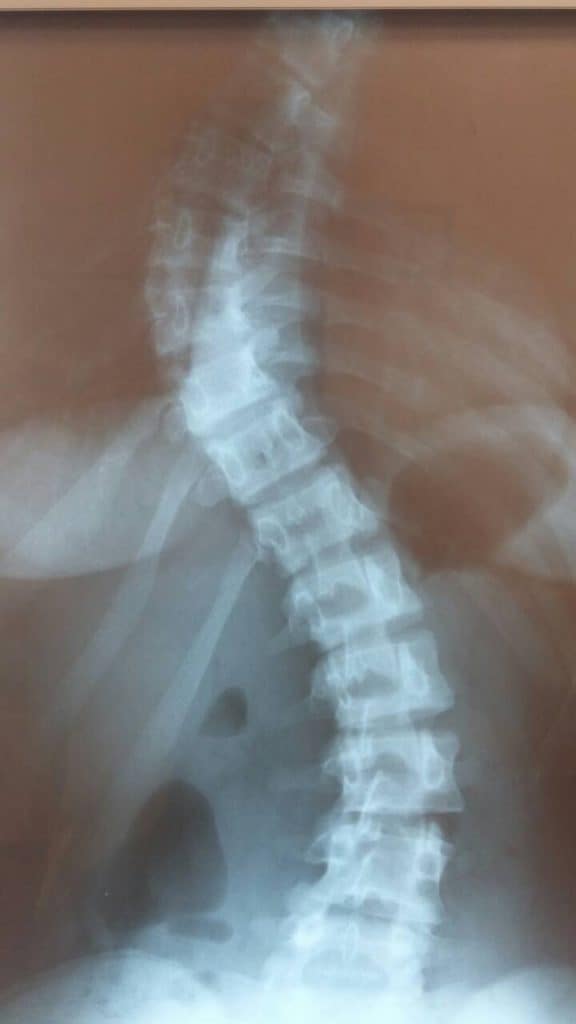

الجنف قبل الجراحة